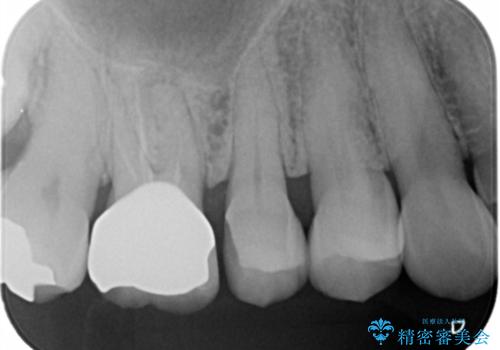

セラミックインレーのやりかえ

- セラミックの詰め物が割れたとの事で来院。

セラミックの詰め物を外して新しくセラミックインレーでやりかえを行いました。

セラミックインレーを外したところ、中にう蝕はありませんでした。

セラミックの詰め物をする事で何年か後に何かしらのエラー(割れる、外れるなど)があった場合、二次的な被害が少ない(う蝕になっていない)のもセラミック治療の特徴です。

歯質とセラミックの間に隙間が生じないので細菌が入り込まないです。